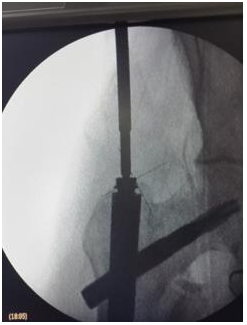

Entry point

1. Dead AP is 10 degree tilt of C arm.

2. Entry by guide wire and special sleeve with multiple options at the trochanteric tip (Figure 9).

Figure 9 Entry by guide wire and special sleeve with multiple options at the trochanteric tip.